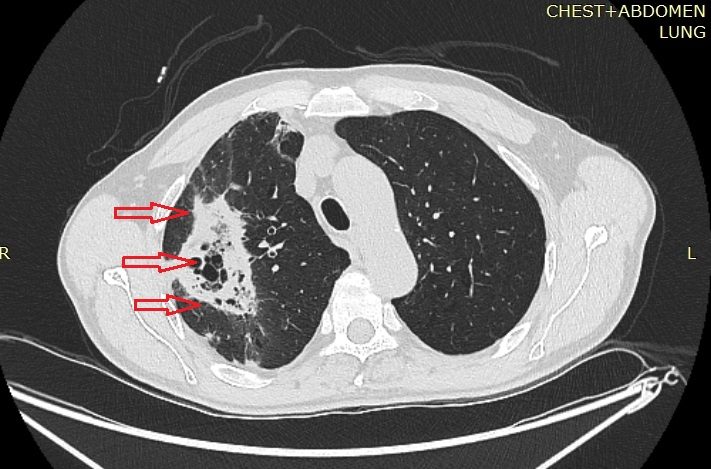

Послеоперационный период протекал гладко, на 4-е сутки пациент был переведен в общее отделение. Особенностью послеоперационного периода являлось быстрое разрешение правосторонней верхнедолевой деструктивной инфаркт-пневмонии, рентгенологическая динамика улучшалась значимо ежедневно. Выполнено контрольное КТ-исследование: правая легочная артерия (рис. 5) и НПВ (рис. 6) проходимы.

Рис. 5. КТ-ангиограмма груди и живота пациента Г. на 6-е сутки послеоперационного периода. Красным овалом указана проходимая правая легочная артерия.

Рис. 6. КТ-ангиограмма груди и живота пациента Г. на 6-е сутки послеоперационного периода. Красными стрелками указана проходимая нижняя полая вена.